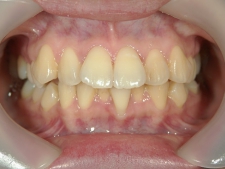

矯正歯科 治療前

矯正歯科(全顎ワイヤー矯正)治療後

全顎ワイヤー矯正 症例(7

)

28歳女性 浜松市西

区在住

治療期間3

年11ヶ月